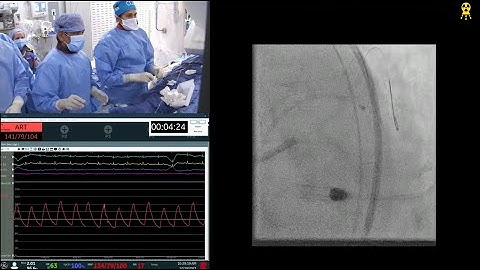

Live Relay - Imaging Guided Complex PCI of Calcified LM/LAD using Rotational Atherectomy and DES